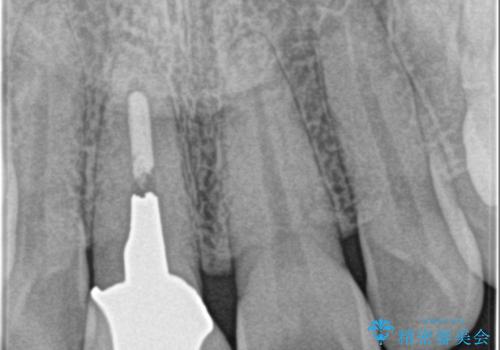

- 前歯が気になるとの事で来院。保険の被せ物(プラスチック素材)メタルの土台が入っていたので

拡大鏡下で全て除去し精密根管治療を行いセラミックの被せ物を装着しました。

- ジルコニアクラウンスペシャル・仮歯 16.5万円 精密根管治療(リトリートメント)・ファイバーコア 12.1万円費用は治療当時の料金となります